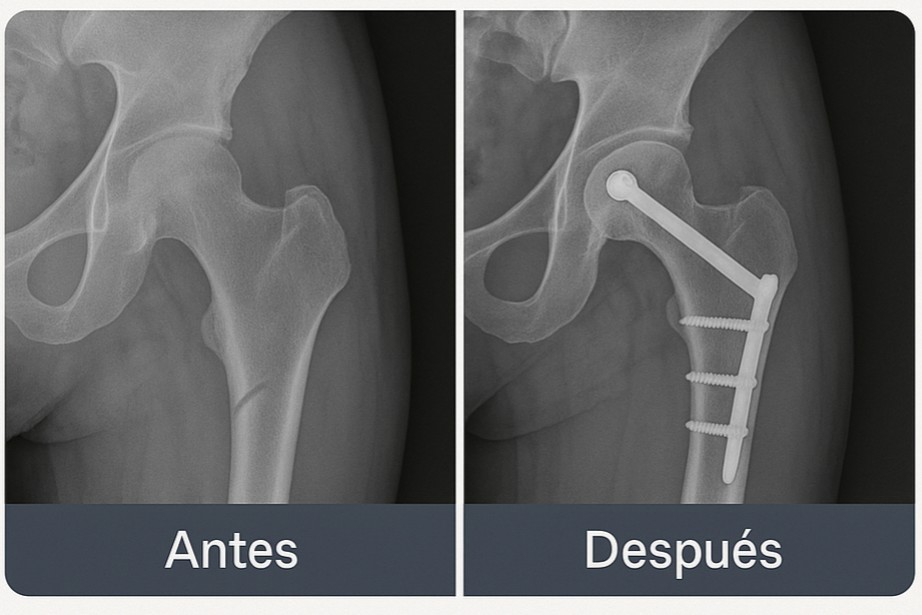

María, 50

Diagnóstico: fractura de fémur.

Enfoque: decisión placa vs. clavo según patrón de fractura y evidencia.

Objetivo: volver a su rutina con estabilidad y buena función.